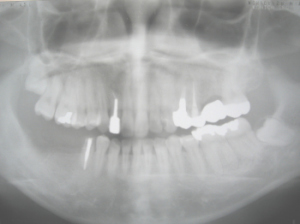

2003/10/30の現状